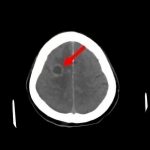

断層撮影

手術前1